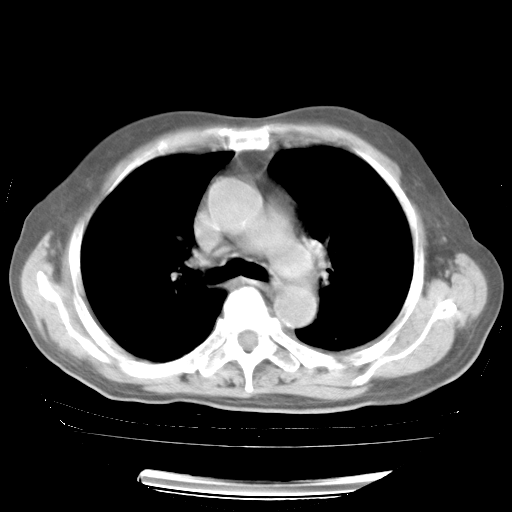

今天部分检查

轻微咳嗽,无痰,(体温正常时)R20次/分,P75次/分,双肺底、腋下可闻及少量捻发音。下肢轻度浮肿。

增加治疗:异烟肼、利福平、乙胺丁醇,静滴左氧氟沙星、参麦注射液。甲强龙从80mg暂减为40mg。

强的松3月1日改为10mg qd,4月1日改为10mg qod。3月份以前的减量过程和环磷酰胺疗程需等明天查看记录(我岳父自己做的记录在他家里)。